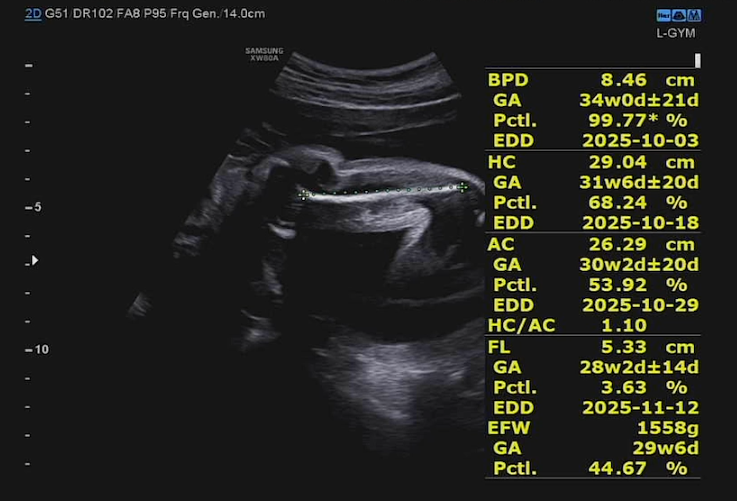

머리가 걷잡을 수 없이 커지고 있다. 왜 때문이냐, 우리 양쪽 집안에 머리가 큰 조상이 없다 이 녀석아 ㅎㅎ 물론 초음파 측정이니 아기가 태어나봐야 정확한 수치를 알 수 있겠지만 정기검진 매 회차 변함없이 머리가 크다고 나오니 신기할 따름이다.

그보다 대퇴골 길이가 짧게 나온 것이 이슈인데, 다리 길이가 반복적으로 짧게 나온다면 정밀 추적 관찰이 필요하다고 한다. 뱃속에서 일어나는 일을 어떻게 도울 수 있는 방법이 없다. 그럼에도 걱정이 없는 건.. 28주 측정치 보다 작아질 수는 없는 거 아닌가? ㅋㅋ 각도에 따라 달리 보이는 초음파의 한계라고 볼 수 있다. 원장님이 수치를 다 보시고도 별 말 없으셨으면 그냥 안심하면 된다 ㅋㅋ 그보다 아이가 1.5kg이 넘어서 오히려 임신주수 보다 1주 크게 잘 성장하고 있다고 하니 또 안심할 수 있었다.

(단위 : cm, g)

- BPD (머리 가로길이)

- 측정치: 8.46 cm

- 해당 주수: 34주 0일 ± 21일

- 백분위수: 99.77%

→ 아기의 머리 가로길이가 평균보다 매우 크게 측정됨. (동일 주수 대비 거의 최상위 수준)

- HC (머리둘레)

- 측정치: 29.04 cm

- 해당 주수: 31주 6일 ± 20일

- 백분위수: 68.24%

→ 머리둘레는 주수보다 약간 크지만 정상 범위.

- AC (복부둘레)

- 측정치: 26.29 cm

- 해당 주수: 30주 2일 ± 20일

- 백분위수: 53.92%

→ 정확히 현재 주수와 거의 일치, 정상적인 성장.

- FL (대퇴골 길이)

- 측정치: 5.33 cm

- 해당 주수: 28주 2일 ± 14일

- 백분위수: 3.63%

→ 다리 길이는 평균보다 짧게 측정됨.

- EFW (추정체중)

- 측정치: 1558 g

- 환산주수: 29주 6일

- 백분위수: 44.67%

→ 체중은 현재 주수와 거의 동일, 중간 정도(정상 범위).